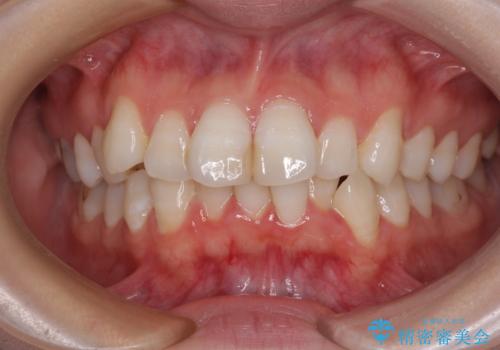

デコボコと口元の突出感を改善 抜歯矯正治療

右上第一小臼歯は歯根癒着により移動せず、左上第二小臼歯は移動はするものの非常に動きが鈍かったため、抜歯したスペースを閉じるまでに非常に時間がかかってしまいました。

患者様には辛抱強く治療にお付き合いいただき、すっきりとした口元に仕上げることができました。